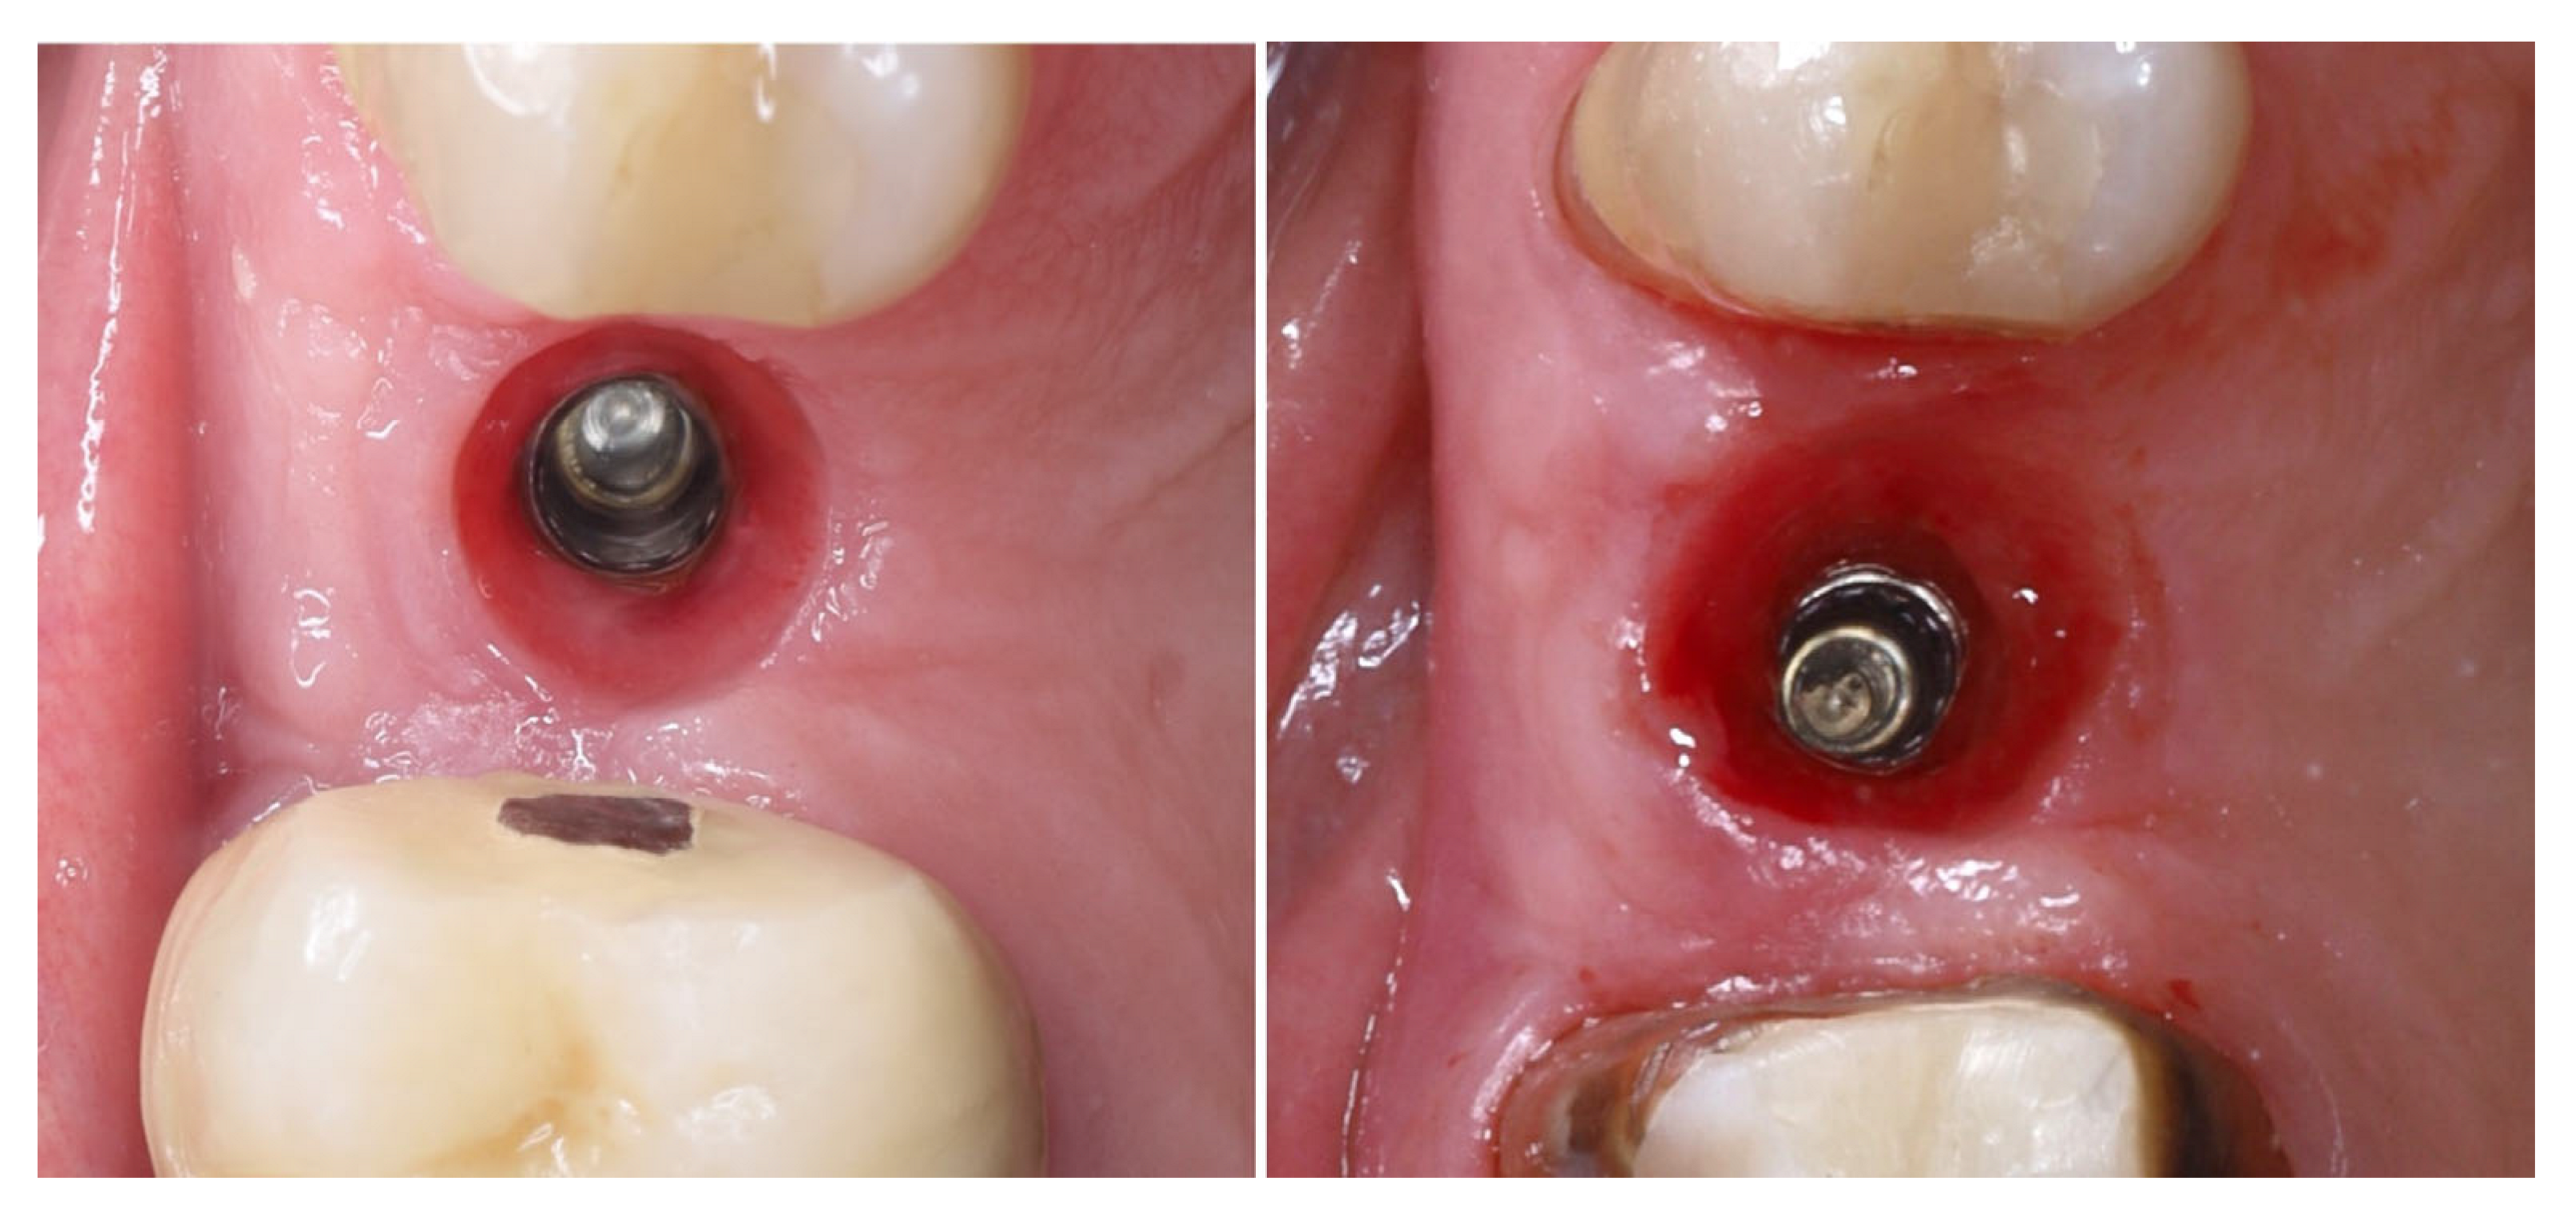

Figure 11 illustrates the peri-implant soft tissue condition 14 days after simultaneous implant placement and roll flap augmentation at suture removal. The buccal flap shows uneventful healing with adequate tissue thickness and favourable contouring around the healing abutment. The mucosal margin appears stable, with absence of dehiscence or inflammation, indicating successful integration of the rolled flap. Different views demonstrate proper adaptation of the peri-implant mucosa, confirming the effectiveness of the roll flap in enhancing buccal soft tissue thickness and achieving a harmonious gingival architecture.

Figure 11.

Clinical views before and after suture removal (14 days post-op).

Three months postoperatively, the peri-implant site demonstrates complete mucosal healing with stable, well-contoured soft tissues. The healing abutment is visible in situ (left), with healthy, keratinized mucosa surrounding the transmucosal interface. Following removal of the healing abutment (middle), the implant platform shows a mature and stable soft tissue collar without signs of inflammation, recession, or dehiscence. The X-ray control reveals stable crestal bone levels without signs of bone remodelling (right) (Figure 12). The roll flap augmentation resulted in increased buccal tissue thickness and harmonious gingival architecture, providing favourable conditions for prosthetic restoration.

Figure 12.

Mature peri-implant mucosa and stable crestal bone after roll flap augmentation (3 months post-op).